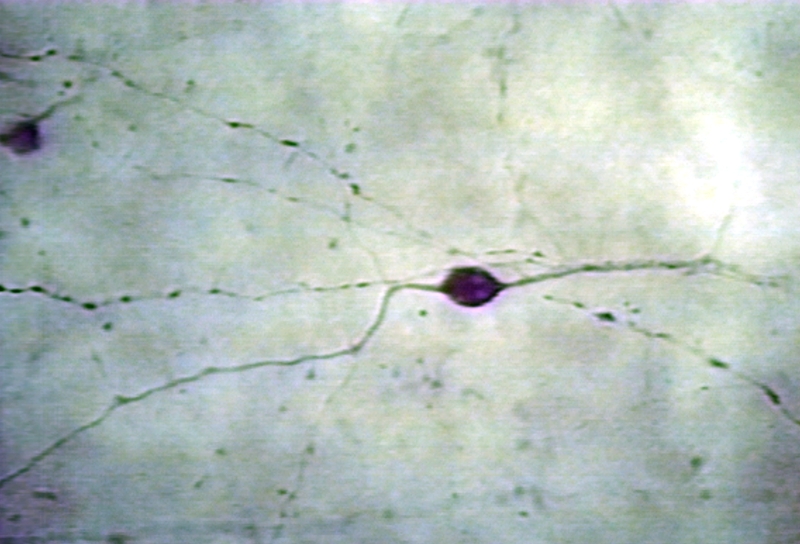

HISTOLOGY: EYE: AMACRINE CELL STAINED FOR SUBSTANCE P; TURTLE RETINA